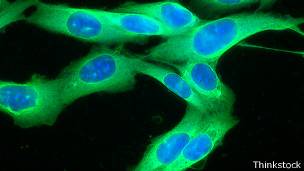

El melanoma es el cáncer de piel más agresivo.

La imagen muestra el melanoma antes del tratamiento.

El tumor aparece reducido tras el tratamiento.